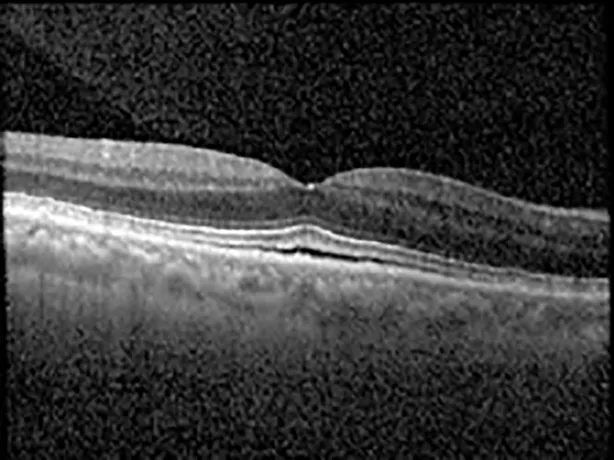

The patient began treatment with oral pemigatinib daily and was followed up for an ophthalmic examination during the second treatment cycle approximately 5 weeks into the treatment process. The patient had at this stage received 28 doses of 13.5 mg per day, which was administered in cycles of 14 on-days and 7 off-days, and had no visual or ophthalmic complaints. The non-corrected VA was OD 20/30 + 1 and OS 20/20. The OCT examinations revealed subfoveal SRF bilaterally. The fundus examination was otherwise unremarkable outside the patient’s prior documented peripheral drusen. Repeat autofluorescence was overall unchanged, though a slight hypofluorescent ring may be visualized in Figure 2. The current pemigatinib protocol recommendation for asymptomatic patients suggests no dose modification; however, with worsening presentation or positive symptoms, it is recommended to withhold pemigatinib. After discussion with the patient’s oncologist, it was decided to continue the medication at this time. Serial monitoring of the patient’s symptoms, vision, and SRF were conducted on specific days during active treatment cycles and days off-cycle to monitor the SRF. Subsequent evaluations demonstrated complete resolution of SRF while off-cycle, and asymptomatic re-accumulation of fluid while on-cycle with varying levels of VA. (Table 1) As we see demonstrated in the table below, in the later stages of the active cycles, such as day 13 of 14 of cycle 2, day 13 of 14 of cycle 3, day 13 of 14 of cycle 4, and day 14 of 14 on cycle 5, the patient’s VA showed no correlative changes based on the presence of SRF. The fluctuations in the patient’s VA certainly occurred, but were likely to be secondary to surface changes, as certain off-cycle days actually presented with lower acuities than days when the SRF was present on OCT examination.

| Cycle, day, on/off | VA OD; OS | CMT OD; OS | OCT OD | OCT OS |

| Cycle 2, day 4, off | 20/30−2; 20/20−2 | 282; 280 | ![]() | ![]() |

Highlights the visual acuity, central macular thickness, and the physical OCT of the macula for this patient in both the right and left eyes during various stages of the patient's chemotherapy treatment cycle.